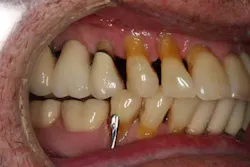

A healthy 67-year-old male presents with generalized severe periodontal disease (Class IV) and several failing restorations of both the maxillary and mandibular arches. He has a partial denture on the bottom that is ill fitting. Tooth No. 11 is broken at the gum line and the distal abutment on the upper left bridge has come loose. He has single implants on site Nos. 10, 24, and 25. Knowing that the prognosis of his current dental situation is poor, he desires a long-term definitive restorative option that would not interfere with his social life, improve his self-image, and provide overall comfort and practical function. He is adamant about not wanting removable prosthetic appliances as part of his future treatment, which left us with the option of using implants. Since the maxillary arch was our immediate primary concern (the lower, for the most part, stable), we discussed several alternatives and finally decided upon the All-On-4 (AO4).

PREOP PHOTOS